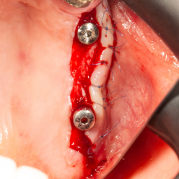

İmplant etrafındaki kemik açıklığını kemik grefti ile tedavi ettiğimiz vakamız